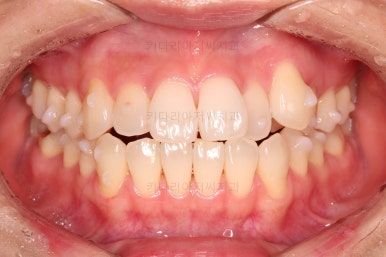

1. 초진

초진 시 입안의 모습입니다.

덧니가 눈에 띄고요.

맞물림이 긴밀하지 못한 상태였습니다.

전반적으로 약간 삐뚤지만 많이 심하다고 보긴 힘들었습니다.

덧니가 있는 방향으로 치열들이 쏠리고 틀어져 중앙선이 맞지 않는 양상이었습니다.